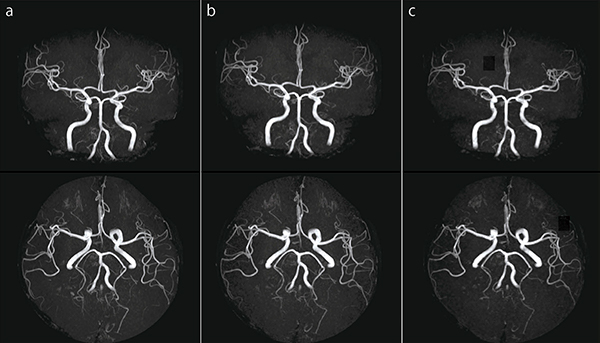

●頭部MRA

図9 aは,IP-RAPIDを使用していない画像です。それに対して図9 b,cは,IP-RAPIDを使用している画像です。空間分解能向上を目的とする場合,Freq/Phaseを大きくする必要があります。しかし,その結果,撮像時間の延長やボクセルサイズが小さくなることによるSNRの低下が発生します。IP-RAPIDを活用することで,これらのリスクを低減させ,高い空間分解能を持った画像を得ることができます。

図9 頭部MRA

a:IP-RAPID off, Phase=2.0, Freq/Phase=256×256, scan time=4:48

b:IP-RAPID on, Phase=1.6, IP-Scan=1.1, Total=1.7, Freq/Phase=288×288, scan time=4:48

c:IP-RAPID on, Phase=1.6, IP-Scan=1.2, Total=1.9, Freq/Phase=320×308, scan time=4:48